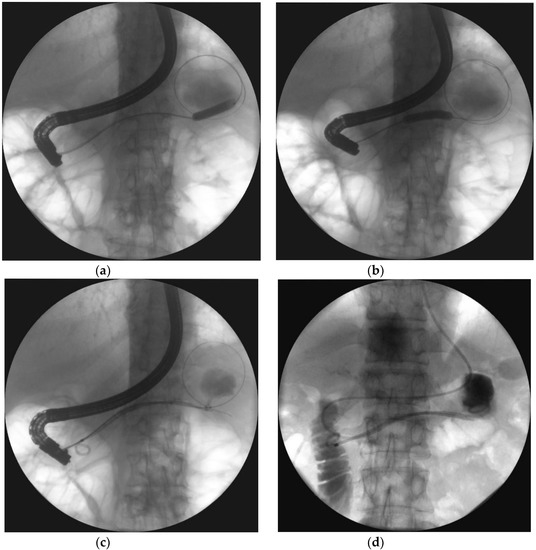

| Single transluminal gateway technique (SGT) | Complete removal of necrotic tissues through a single fistula created between the cavity of necrotic collection and the lumen of gastrointestinal tract (stomach or duodenum). Endoprosthesis and drains were inserted through the single fistula in the case of unilocular necrotic collections. |

| Multiple transluminal gateway technique (MTGT) | The creation of multiple transmural tracts between the gastrointestinal lumen and the WON cavity. In MTGT another transmural tract between the necrotic cavity and the gastrointestinal lumen was performed in case of multilocular necrotic collections divided by septa. |

| Single transluminal gateway transcystic multiple drainage (SGTMD) | Additional transmural drainage of extensive necrosis through a single fistula. Stents and nasocystic drains were introduced in the subcavities of WOPN through the single transmural tract and canals between necrotic subcavities. |

- Varadarajulu, S.; Phadnis, M.A.; Christein, J.D.; Wilcox, C.M. Multiple transluminal gateway technique for EUS-guided drainage of symptomatic walled-off pancreatic necrosis. Gastrointest. Endosc. 2011, 74, 74–80. [Google Scholar] [CrossRef]

- Jagielski, M.; Smoczyński, M.; Adrych, K. Endoscopic treatment of multilocular walled-off pancreatic necrosis with the multiple transluminal gateway techniques. Wideochir. Inne. Tech. Maloinwazyjne. 2017, 12, 199–205. [Google Scholar] [CrossRef] [PubMed]

- Mukai, S.; Itoi, T.; Sofuni, A.; Itokawa, F.; Kurihara, T.; Tsuchiya, T.; Ishii, K.; Tsuji, S.; Ikeuchi, N.; Tanaka, R.; et al. Novel single transluminal gateway transcystic multiple drainages after EUS-guided drainage for complicated multilocular walled-off necrosis (with videos). Gastrointest. Endosc. 2014, 79, 531–535. [Google Scholar] [CrossRef]

- Mukai, S.; Itoi, T.; Sofuni, A.; Itokawa, F.; Kurihara, T.; Tsuchiya, T.; Ishii, K.; Tsuji, S.; Ikeuchi, N.; Tanaka, R.; et al. Expanding endoscopic interventions for pancreatic pseudocyst and walled-off necrosis. J. Gastroenterol. 2015, 50, 211–220. [Google Scholar] [CrossRef]

- Jagielski, M.; Smoczyński, M.; Adrych, K. Single transluminal gateway transcystic multiple drainage for extensive walled-off pancreatic necrosis—A single center experience. Prz. Gastroenterol. 2018, 13, 242–248. [Google Scholar]

- Jagielski, M.; Smoczyński, M.; Adrych, K. Endoscopic treatment of extensive walled-off pancreatic necrosis with the use of single transluminal gateway transcystic multiple drainage (SGTMD). Pol. Przegl. Chir. 2018, 90, 54–59. [Google Scholar] [CrossRef]